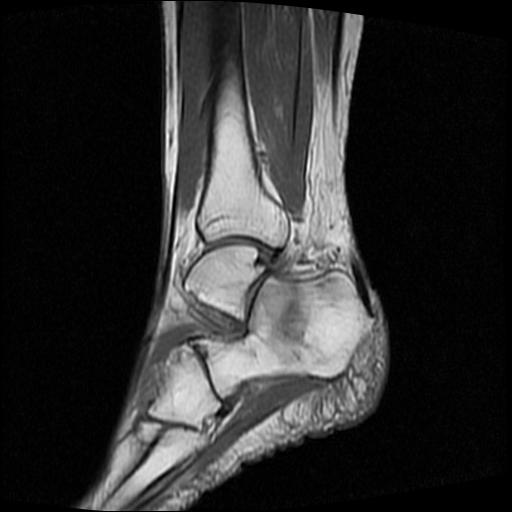

标题: MRI0968:女性,70岁,跟骨信号异常 [打印本页]

标题: MRI0968:女性,70岁,跟骨信号异常

女性,70岁,右侧跟骨疼痛2个月,负重时加剧,不负重时不疼。

胫骨下段,跟骨、距骨可见斑片状异常信号区;考虑:转移瘤

考虑  跟骨骨髓炎

考虑: 跟骨骨髓炎.

跟骨cr片正常。

跟骨病灶呈片状,边界模糊,可否考虑隐匿性骨折呢?

跟骨长t1长t2信号异常,边缘模糊(肿瘤一般边界清楚,故肿瘤不考虑),压脂像呈高信号--骨髓水肿(炎症?)。